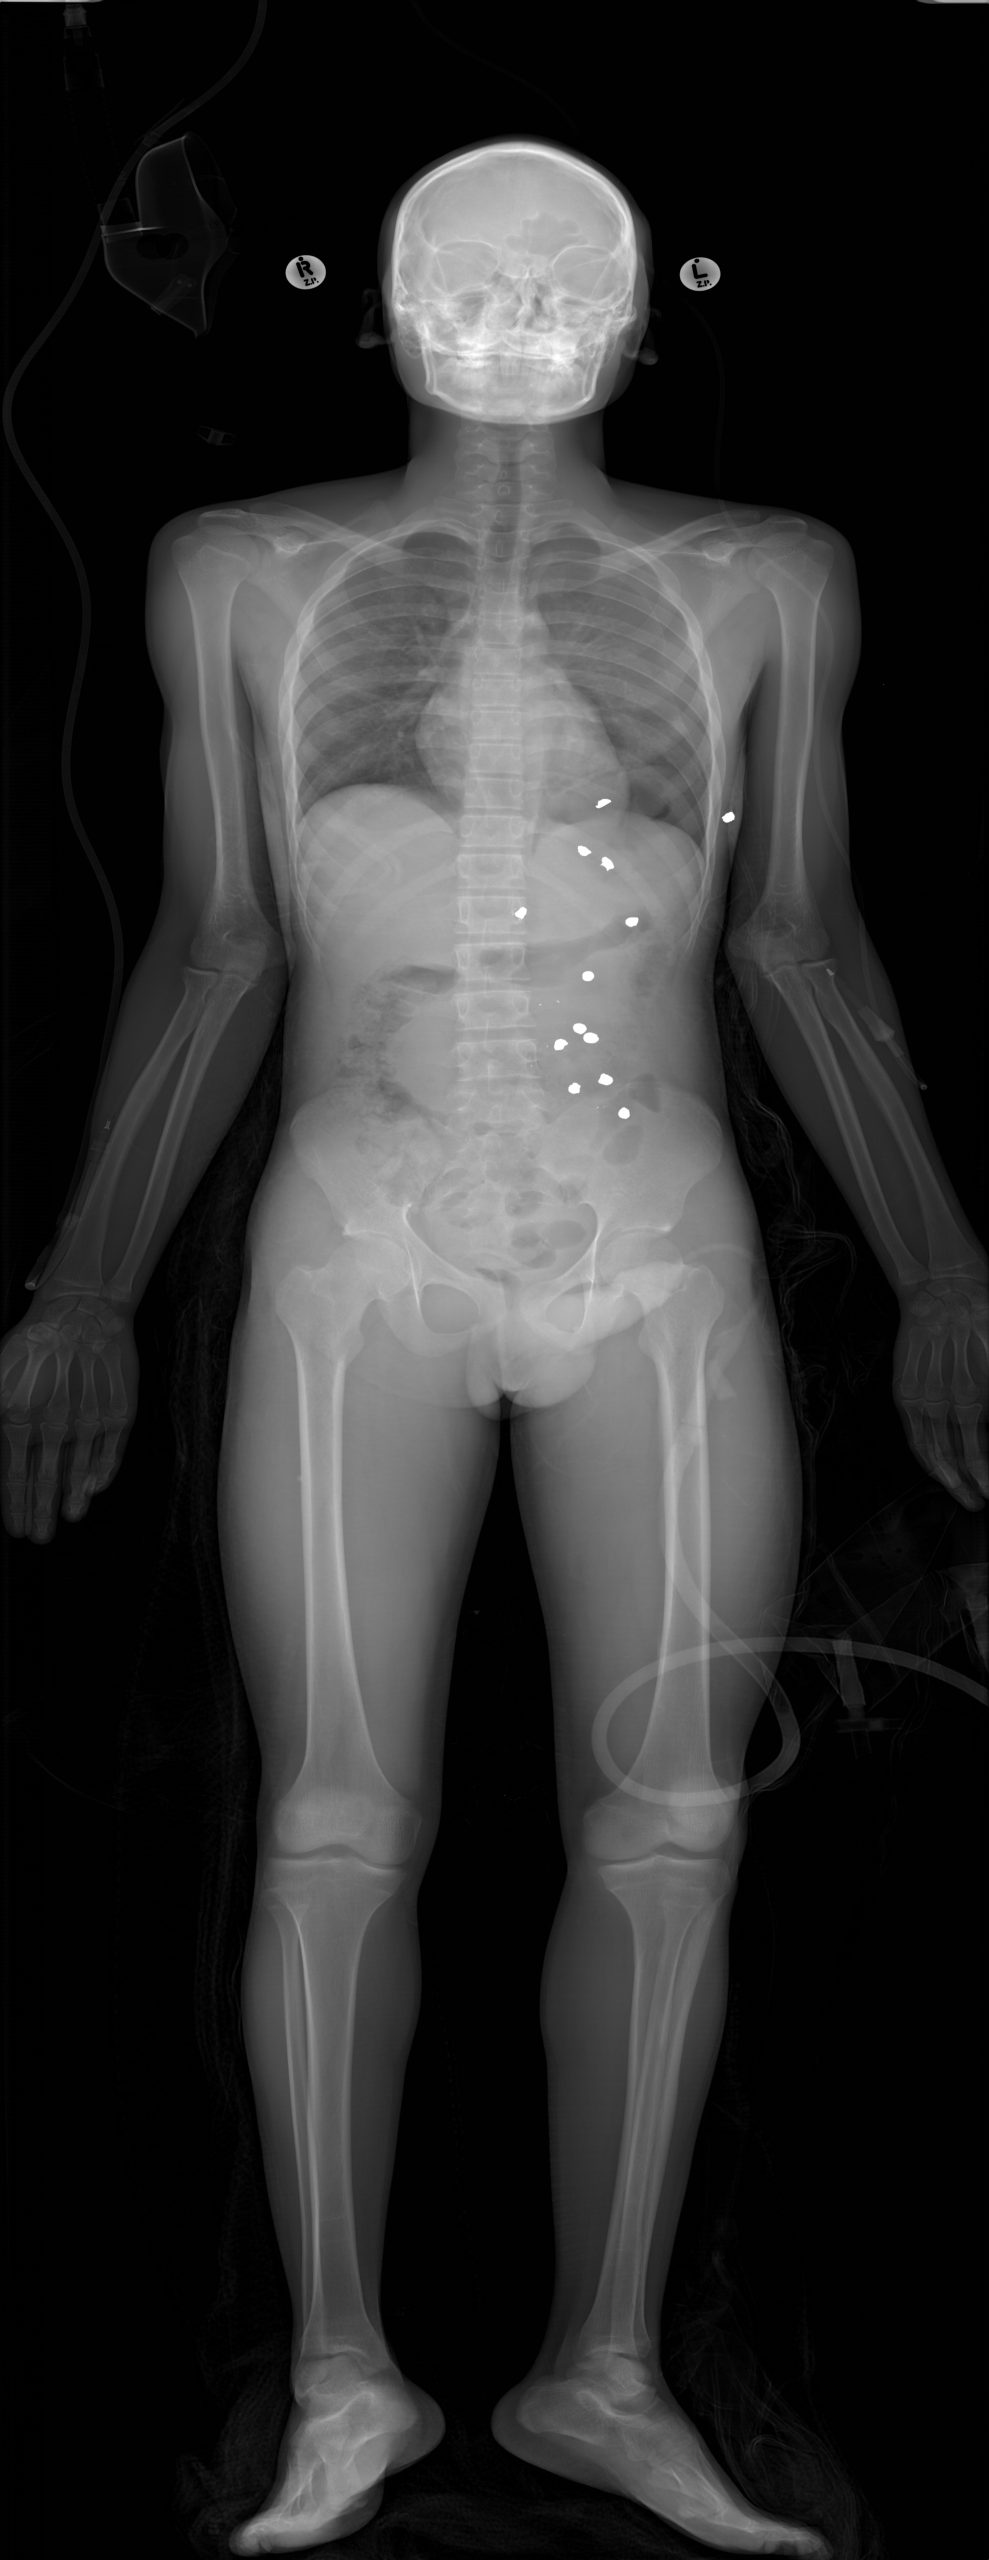

Klinik Görüntüler

Yukarıdaki örnek görüntüler, Lodox Xmplar-dr sisteminin her yaş ve vücut tipindeki hastalarda sunduğu yüksek çözünürlüklü tam vücut görüntüleme kapasitesini göstermektedir. Pediatrik hastalardan erişkinlere, düşük kilolu bireylerden yüksek vücut kitle indeksine sahip hastalara kadar geniş bir hasta grubunda net anatomik detay elde edilebilmektedir. Linear slot-scanning teknolojisi sayesinde kemik, yumuşak doku ve yabancı cisimler tek çekimde, ortalama 13–16 saniyede ve ultra düşük radyasyon dozu ile görüntülenir. Bu özellik, özellikle travma ve acil servis koşullarında hem hızlı tanı koymayı hem de radyasyona bağlı riskleri en aza indirmeyi mümkün kılar.